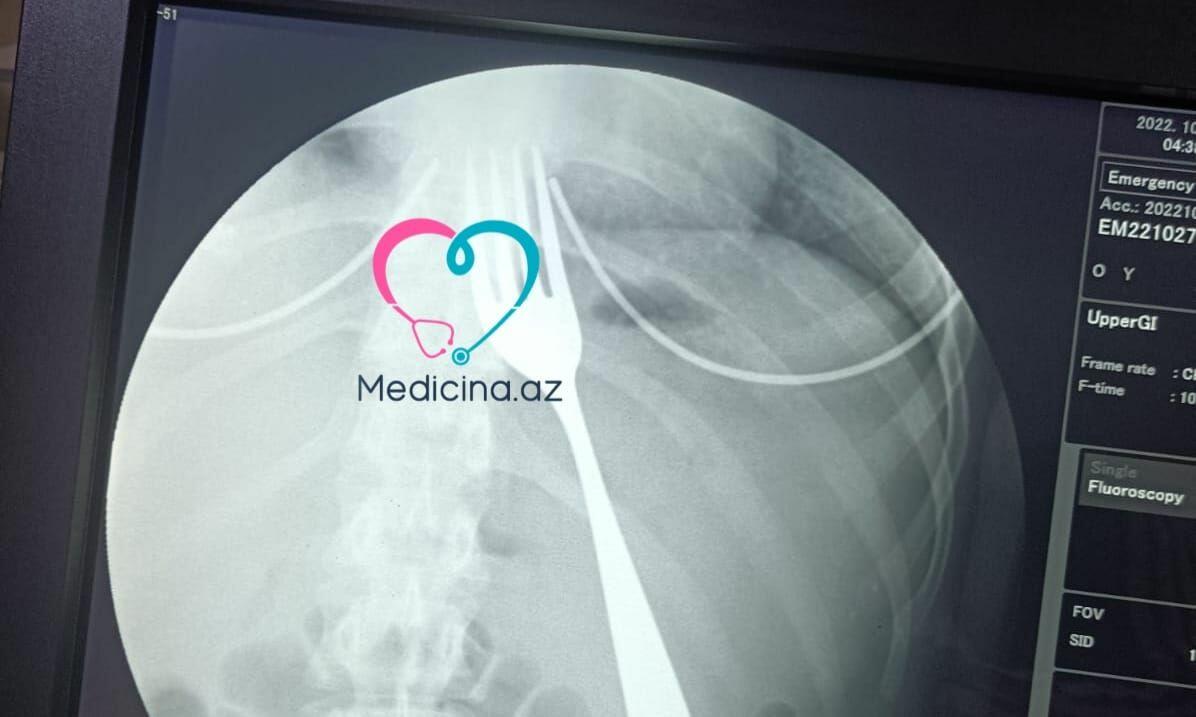

Bakıda 21 yaşlı gənc qız çəngəl udub.

2001-ci il təvəllüdlü Aysel Həmidova (Ad şərtidir) özün qusdurmaq üçün çəngəldən istifadə edib. Bu zaman çəngəl boğazına girib.

Dərhal o, 1 saylı Kliniki Tibbi Mərkəzin (“Semaşko” xəstəxanası) təcili yardım şöbəsinə gətirilib. Lakin onu paytaxtdakı özəl xəstəxanalardan birinə göndəriblər.